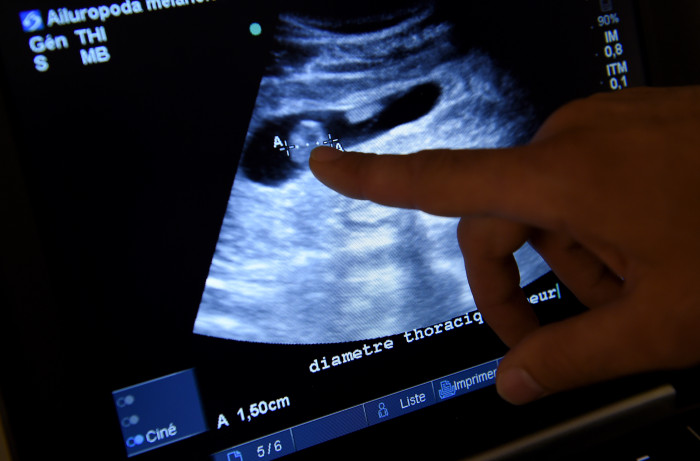

La novedad que ofrece este nuevo beneficio es que se incluye la fertilización in vitro, para los pacientes del Fondo Nacional de Salud (Fonasa) en clínicas y hospitales.

Con esta medida, inédita en nuestro país, el Ejecutivo establece por primera vez financiamiento para el tratamiento de fertilización in vitro en el sector privado, uno de los métodos más costosos para tratar la infertilidad, y garantizaría un subsidio de un 50% para los pacientes de Fonasa, según consignó en un reportaje La Tercera.

“Vas a necesitar hacer una fecundación fuera del cuerpo, lo que se le llama fecundación in vitro, que en el fondo es sacar el óvulo fuera del cuerpo y hacerlo fecundar afuera“, explicó a Página 7.